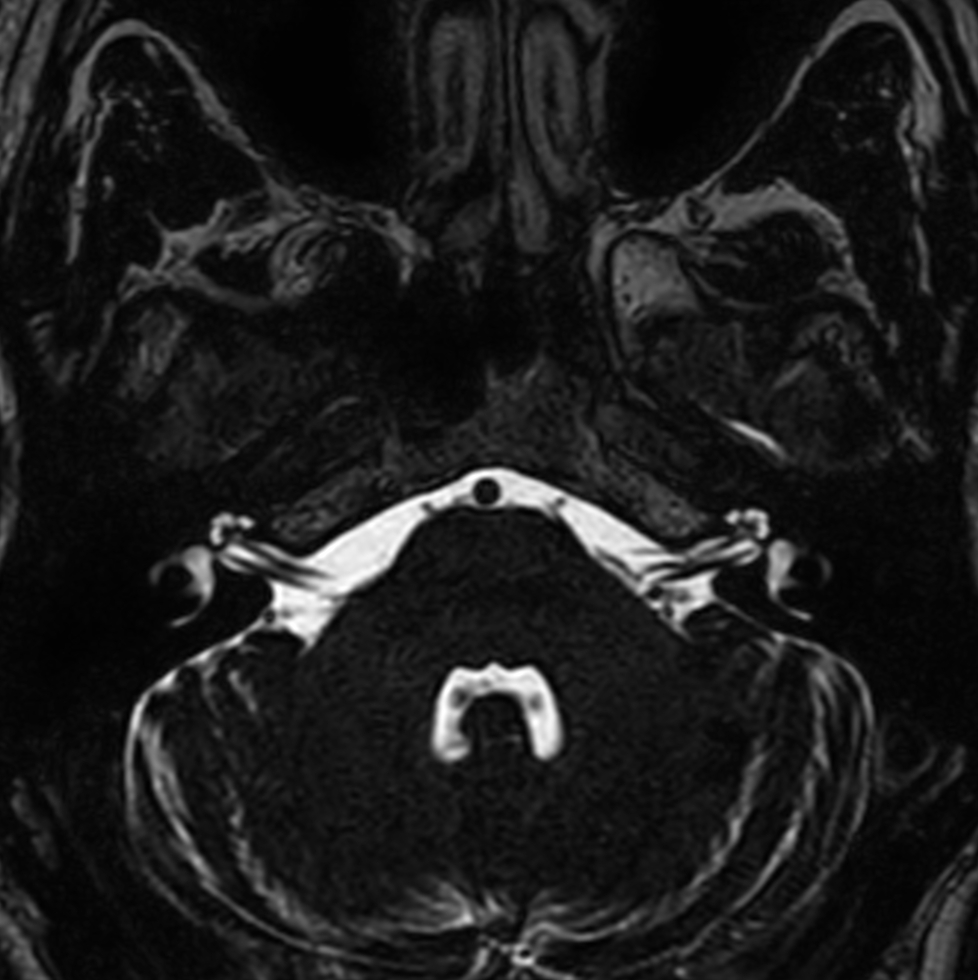

Axial T2w 3D DRIVE (IAC)